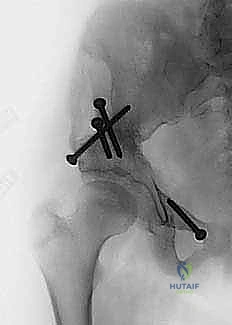

باستخدام أدوات خاصة، يقوم الدكتور هطيف بتدوير التجويف الحقي الحر في ثلاثة أبعاد (للأمام، وللخارج، وللأسفل) حتى يغطي رأس عظم الفخذ بشكل مثالي وميكانيكي سليم. يتم التحقق من الزاوية الجديدة فوراً داخل غرفة العمليات باستخدام جهاز الأشعة السينية المتحرك (C-arm).

5. التثبيت القوي (Fixation)

بمجرد الوصول إلى الوضع المثالي، يتم تثبيت العظام في مكانها الجديد باستخدام براغي معدنية قوية من التيتانيوم أو دبابيس (K-wires). هذا التثبيت يضمن التحام العظام بشكل صحيح خلال فترة التعافي.